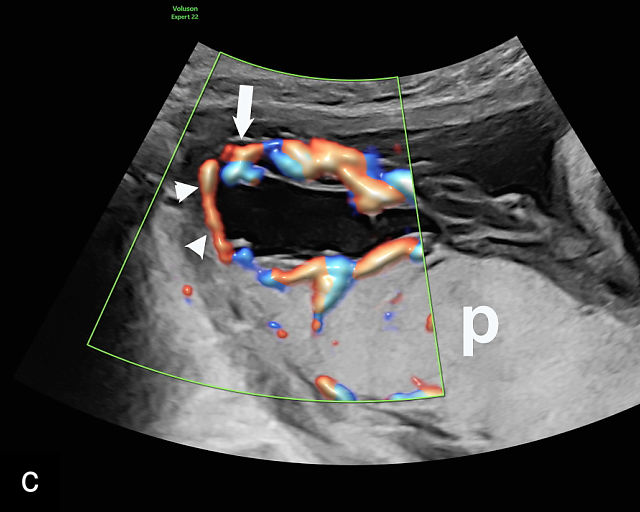

There are three types of vasa previa.30,262 In Type 1, the cord inserts into the membranes rather than the placenta. Unprotected vessels then traverse the membranes over the cervix to insert into the placenta (Figure 21a; Video 12). In Type 2, unprotected vessels running through the membranes over the cervix connect the main placental lobe with an accessory lobe (Figure 21b).263 In Type 3, there is generally a normal placental cord insertion, and unprotected vessels exit one placental edge, run through the membranes over the cervix and then boomerang to insert into the placental edge at another site (Figure 21c).25,28,29,264 Regardless of the type, all these expose the fetus to the same risks.

21